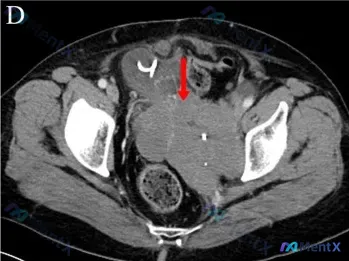

整理了一个挺有警示意义的病例资料,核心是2022年CT发现的盆腔巨大占位,想和大家聊聊这个病例的分析思路——这里其实很容易被惯性思维带偏。 --- 先看核心影像表现 是一张盆腔CT软组织窗横断面: - 盆腔中部有一个巨大软组织密度肿块,占据大部分盆腔,有明显占位效应,推挤了膀胱和周围肠管; - 关键...

最近看到一个挺值得琢磨的病例,整理了一下资料和思路,和大家分享讨论。 --- 先看核心临床信息 - 背景:患者接受了6个周期的免疫治疗 - 主诉/关注点:发现左臀部软组织结节 - 已知影像测量:左臀部软组织结节大小约1.6x5.8cm - 补充影像(盆腔CT软组织窗): 影像中心是盆腔中央区域的占位...